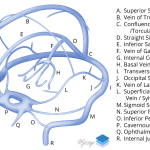

- Hyperdensity in the left transverse sinus, straight sinus, vein of Galen, and in veins coursing along the left cerebellar hemisphere

- Scattered linear hyperdensities within sulci in the bilateral cerebral and cerebellar hemispheres

- Small acute parenchymal hemorrhage in the high right frontal lobe

- Hypodensity in the left temporo-occipital region

- Venous sinus thrombosis with associated hemorrhage and parenchymal edema

Hyperdensity in the left transverse sinus, straight sinus, vein of Galen, and in a vein coursing along the left cerebellar hemisphere concerning for venous thrombosis. Small acute parenchymal hemorrhage in the high right frontal lobe raises concern for superior sagittal sinus and/or cortical vein thrombosis as well. Recommend brain MRI with and without contrast for further evaluation.

Scattered linear hyperdensities within sulci in the bilateral cerebral and cerebellar hemispheres, which may represent small volume subarachnoid hemorrhage and/or additional small thrombosed veins. No hydrocephalus.

Hypodensity in the left temporo-occipital region consistent with edema/developing venous infarct.